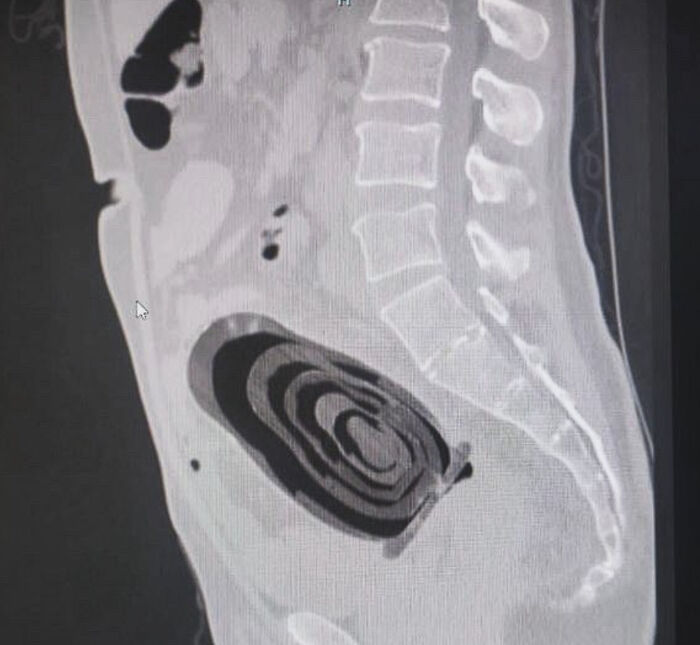

Un hombre de 66 años cayó "accidentalmente" sobre una muñeca matrioska la pasada Nochebuena en Roma.